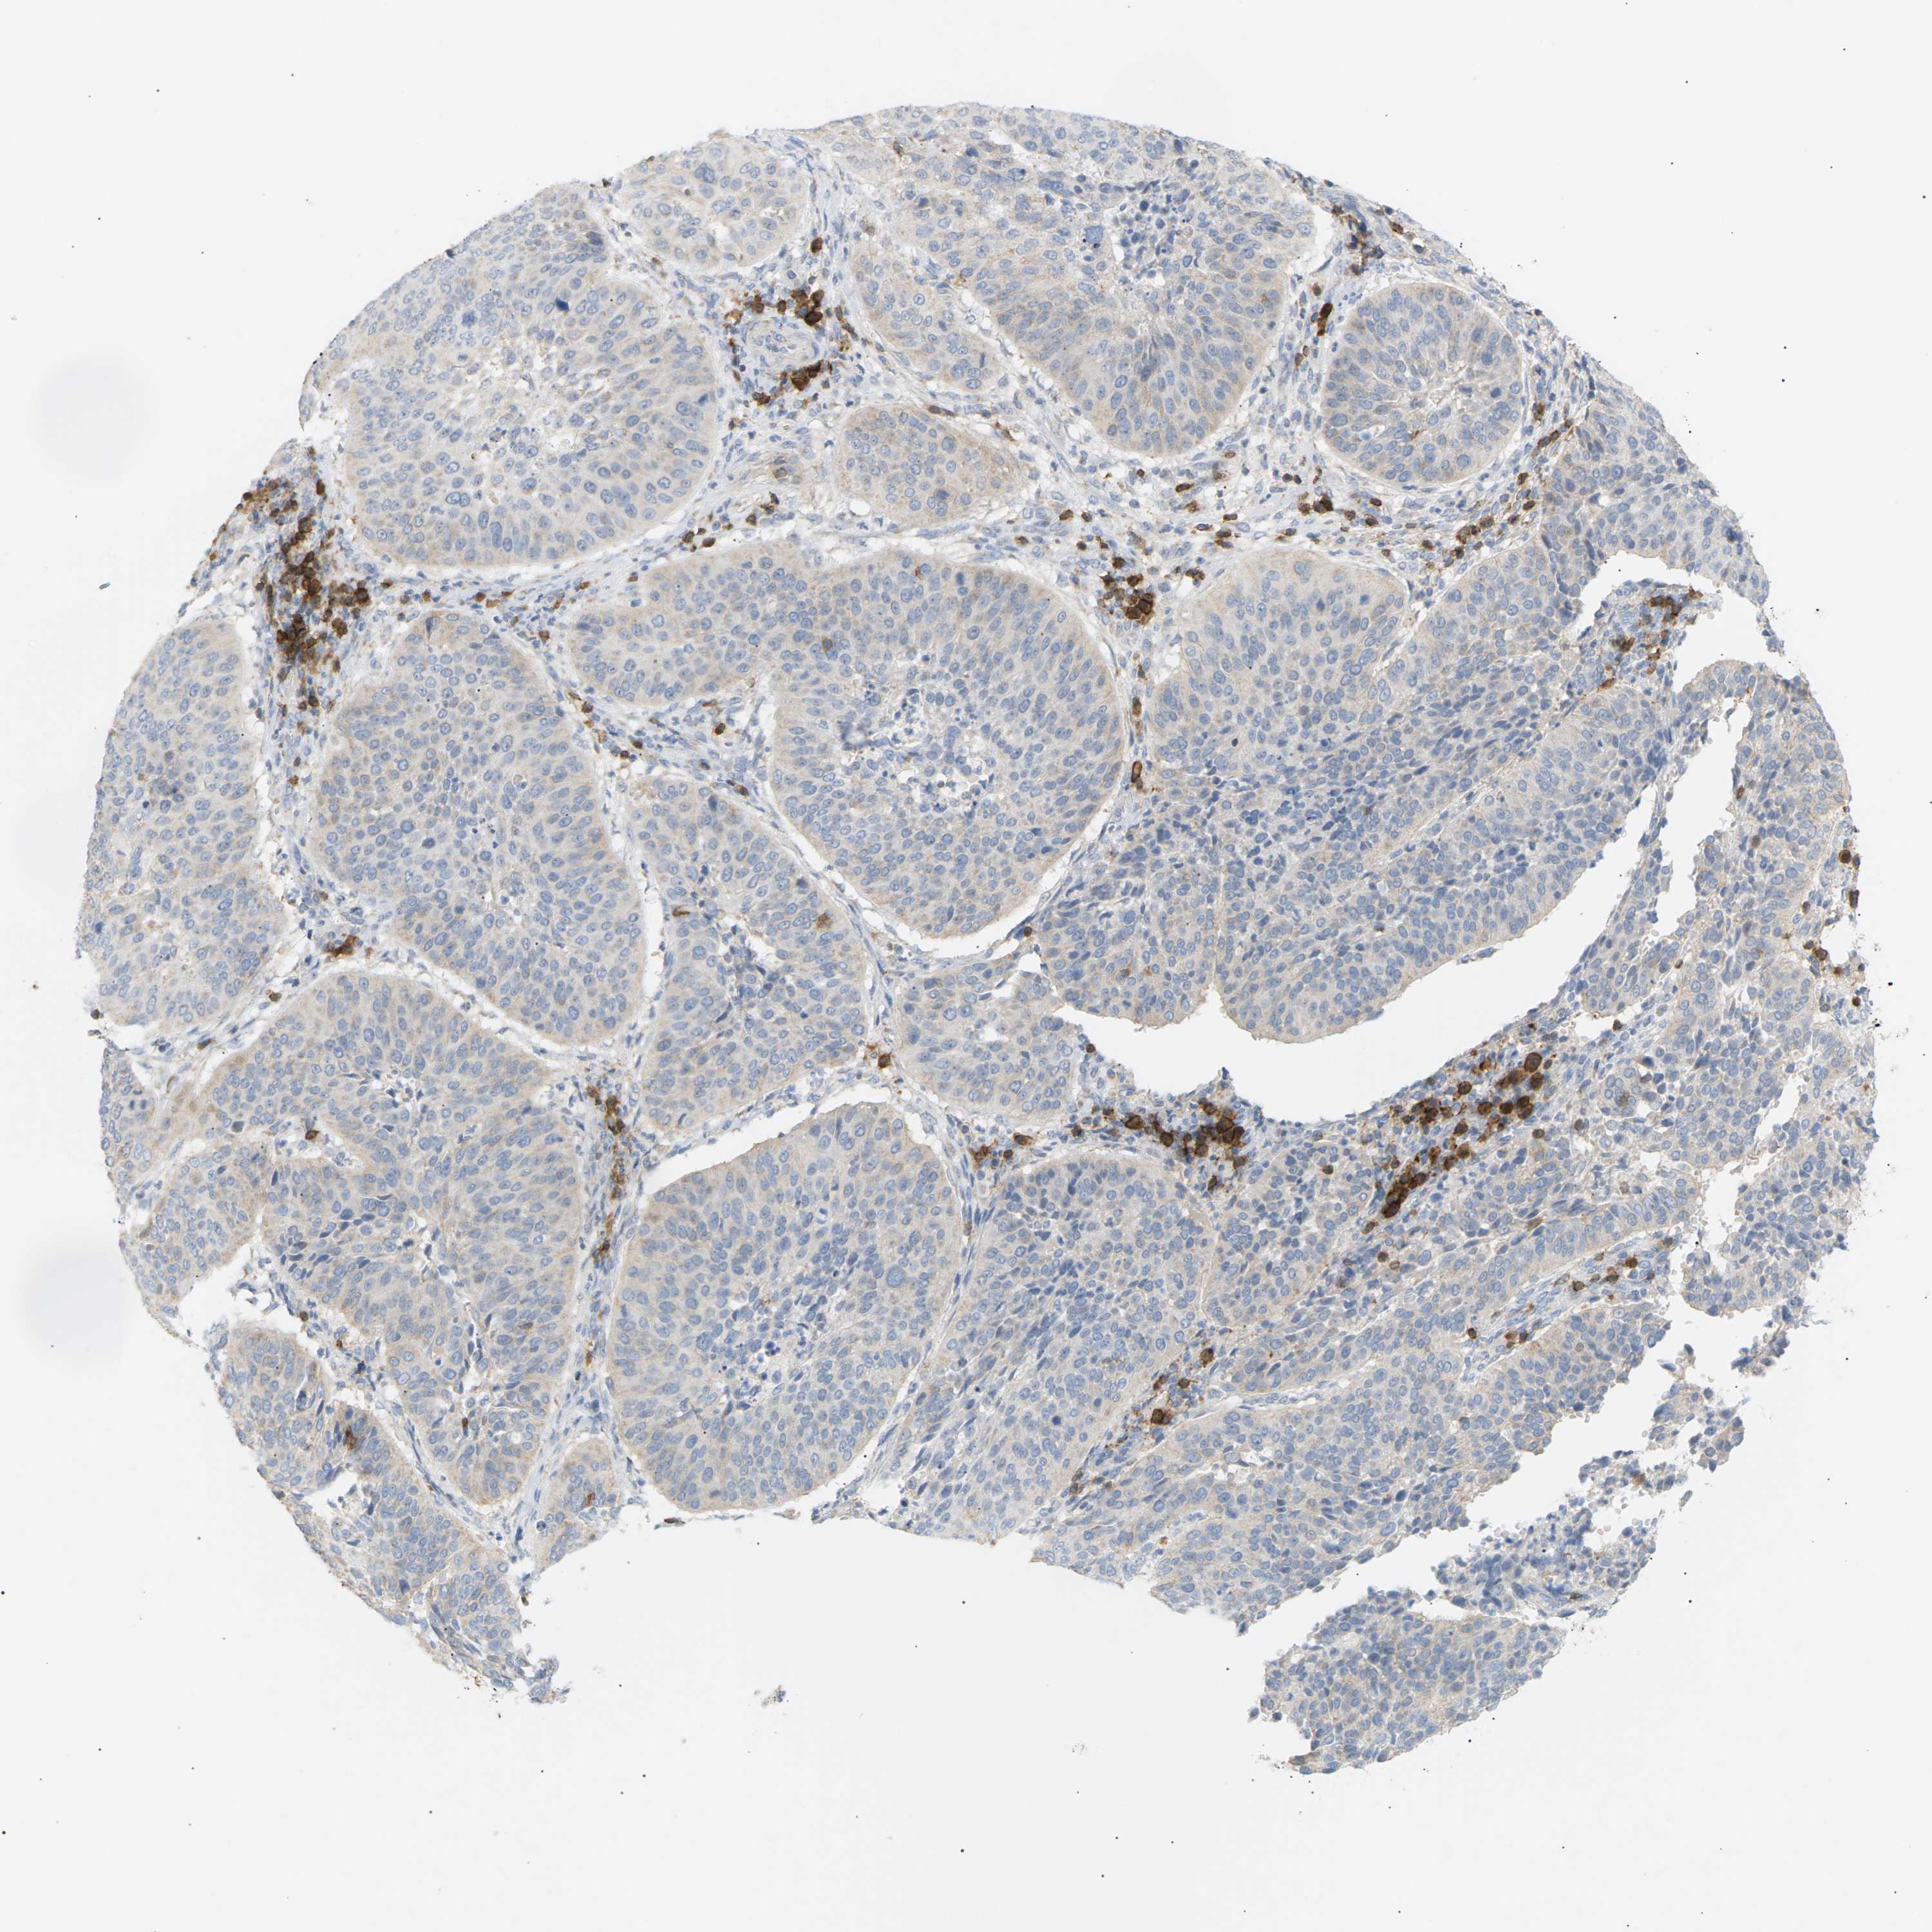

CERVICAL CANCER - Protein expressioni

A mouse-over function shows sample information and annotation data. Click on an image to view it in a full screen mode. Samples can be filtered based on level of antibody staining by selecting one or several of the following categories: high, medium, low and not detected. The assay and annotation is described here.

Note that samples used for immunohistochemistry by the Human Protein Atlas do not correspond to samples in the TCGA dataset.

Antibody stainingi

Antibody staining in the annotated cell types in the current human tissue is reported as not detected, low, medium, or high, based on conventional immunohistochemistry profiling in selected tissues. This score is based on the combination of the staining intensity and fraction of stained cells.

Each image is clickable and will lead to virtual microscopy that enables deeper exploration of all samples and also displays staining intensity scores, fraction scores and subcellular localization as well as patient and tissue information for each sample.

Antibody CAB015363

Staining

High

Medium

Low

Not detected

Intensity

Strong

Moderate

Weak

Negative

Quantity

>75%

75%-25%

<25%

None

Location

Nuclear

Cytoplasmic/membranous

Cytoplasmic/membranous,nuclear

Squamous cell carcinoma, NOS